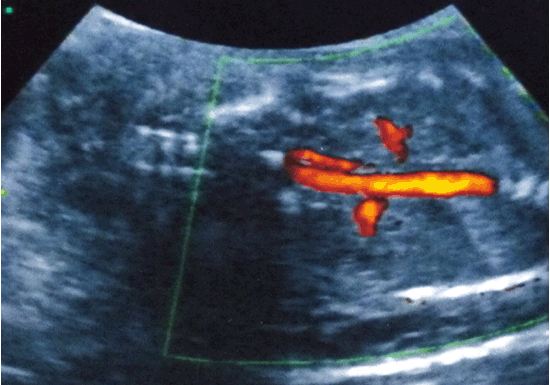

Hình 2. Không ghi nhận bất thường trên Doppler động mạch rốn